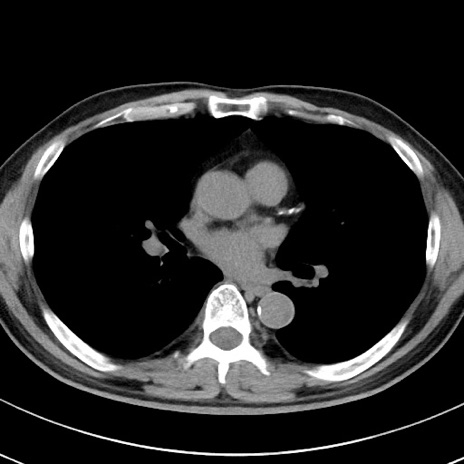

【腹部TIPS】症例29 参考症例 CT(横断像)

症例

70歳代男性